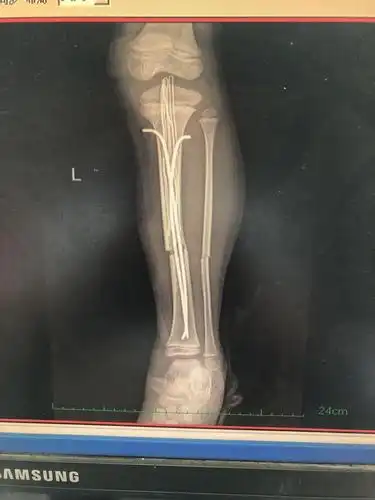

胫腓骨骨折髓内钉固定 曲阳县第二医院骨科

左胫骨骨折